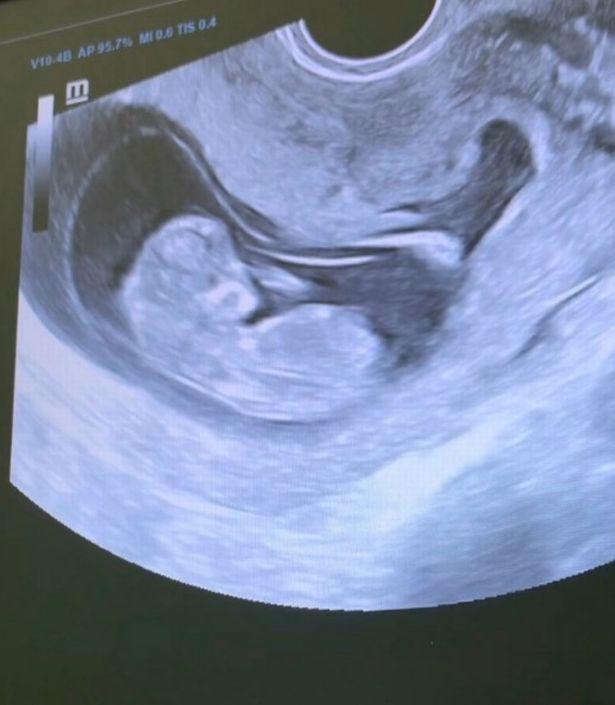

在分享婚礼视频前 , 玛丽娜发放了一段超声波视频 , 可以看到新生宝宝在妈妈腹中的移动 。

玛丽娜透露 , 宝宝“看起来像是一个男孩” , 已经有5厘米长 , 她已经怀孕了11到12周 。

玛丽娜表示 , 当看着自己未出生的宝宝在肚子里移动时 , 她感到非常激动 。

▲玛丽娜分享了婴儿的超声影像